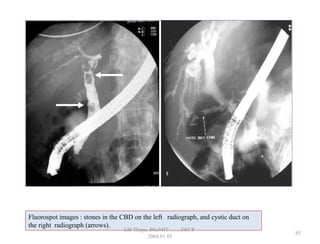

Fluorospot images : stones in the CBD on the left radiograph, and cystic duct on

the right radiograph (arrows).

• 80.

Fluorospot images :stones in the CBD on the left radiograph, and cystic duct on the right radiograph (arrows). 85 GB Thapa, BScMIT.........ERCP 2068.01.05